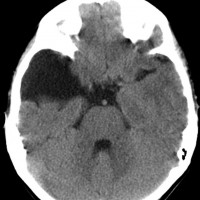

トルコ鞍内くも膜のう胞:症候性

症候性くも膜のう胞 下垂体機能不全を呈したもの

高齢の女性が副腎皮質機能低下,甲状腺機能低下,高プロラクチン血症,低ナトリウム血症で発症しました。負荷試験の結果は下垂体機能低下症によるものでした。

トルコ鞍内後方にくも膜のう胞があり,下垂体は前方に押し付けられて扁平化しています。このようなものでも通常は無症候性で,症状を出すことは珍しいと言えます。

治療は経鼻手術でのう胞を破るだけです。その手術で,再発することも再発しないこともあります。